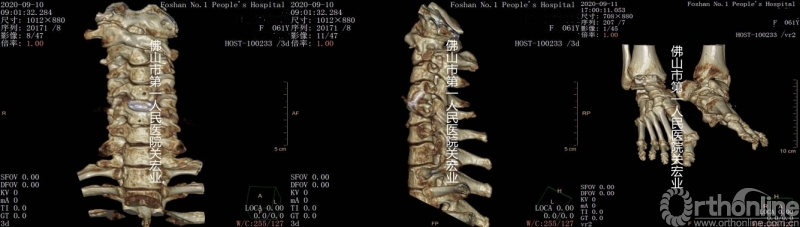

术前CT

术前CTA